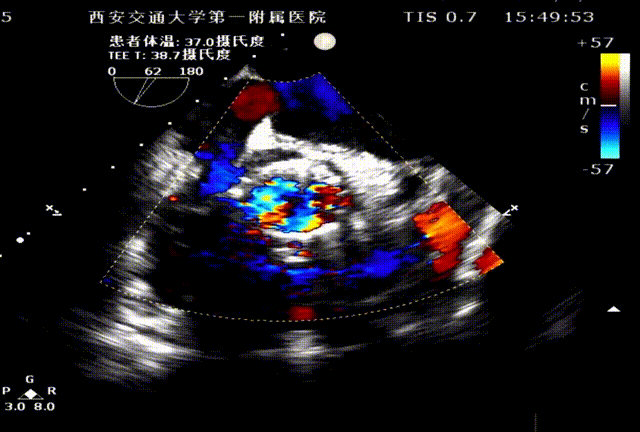

食道超声瓣架位置正确,启闭良好,未见明显瓣周漏: